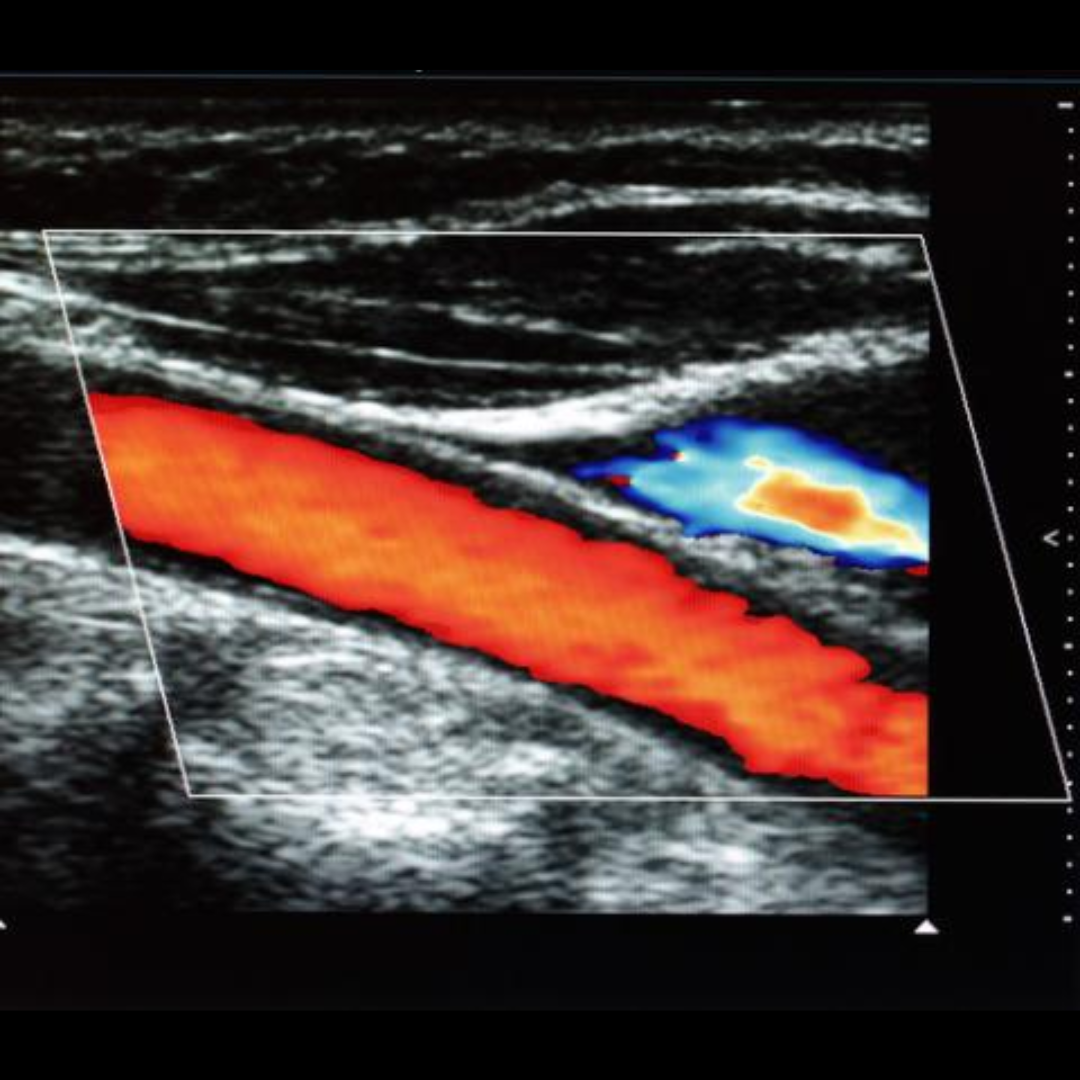

Ecografía Doppler Arterial

La ecografía Doppler arterial es un estudio de ecografías que estudia las diferentes ramas arterias de miembro superior o inferior, evaluando su calibre y descartando la presencia de placas ateromatosas o estrechez que indiquen un flujo lento, por lo tanto descarta insuficiencia arterial.